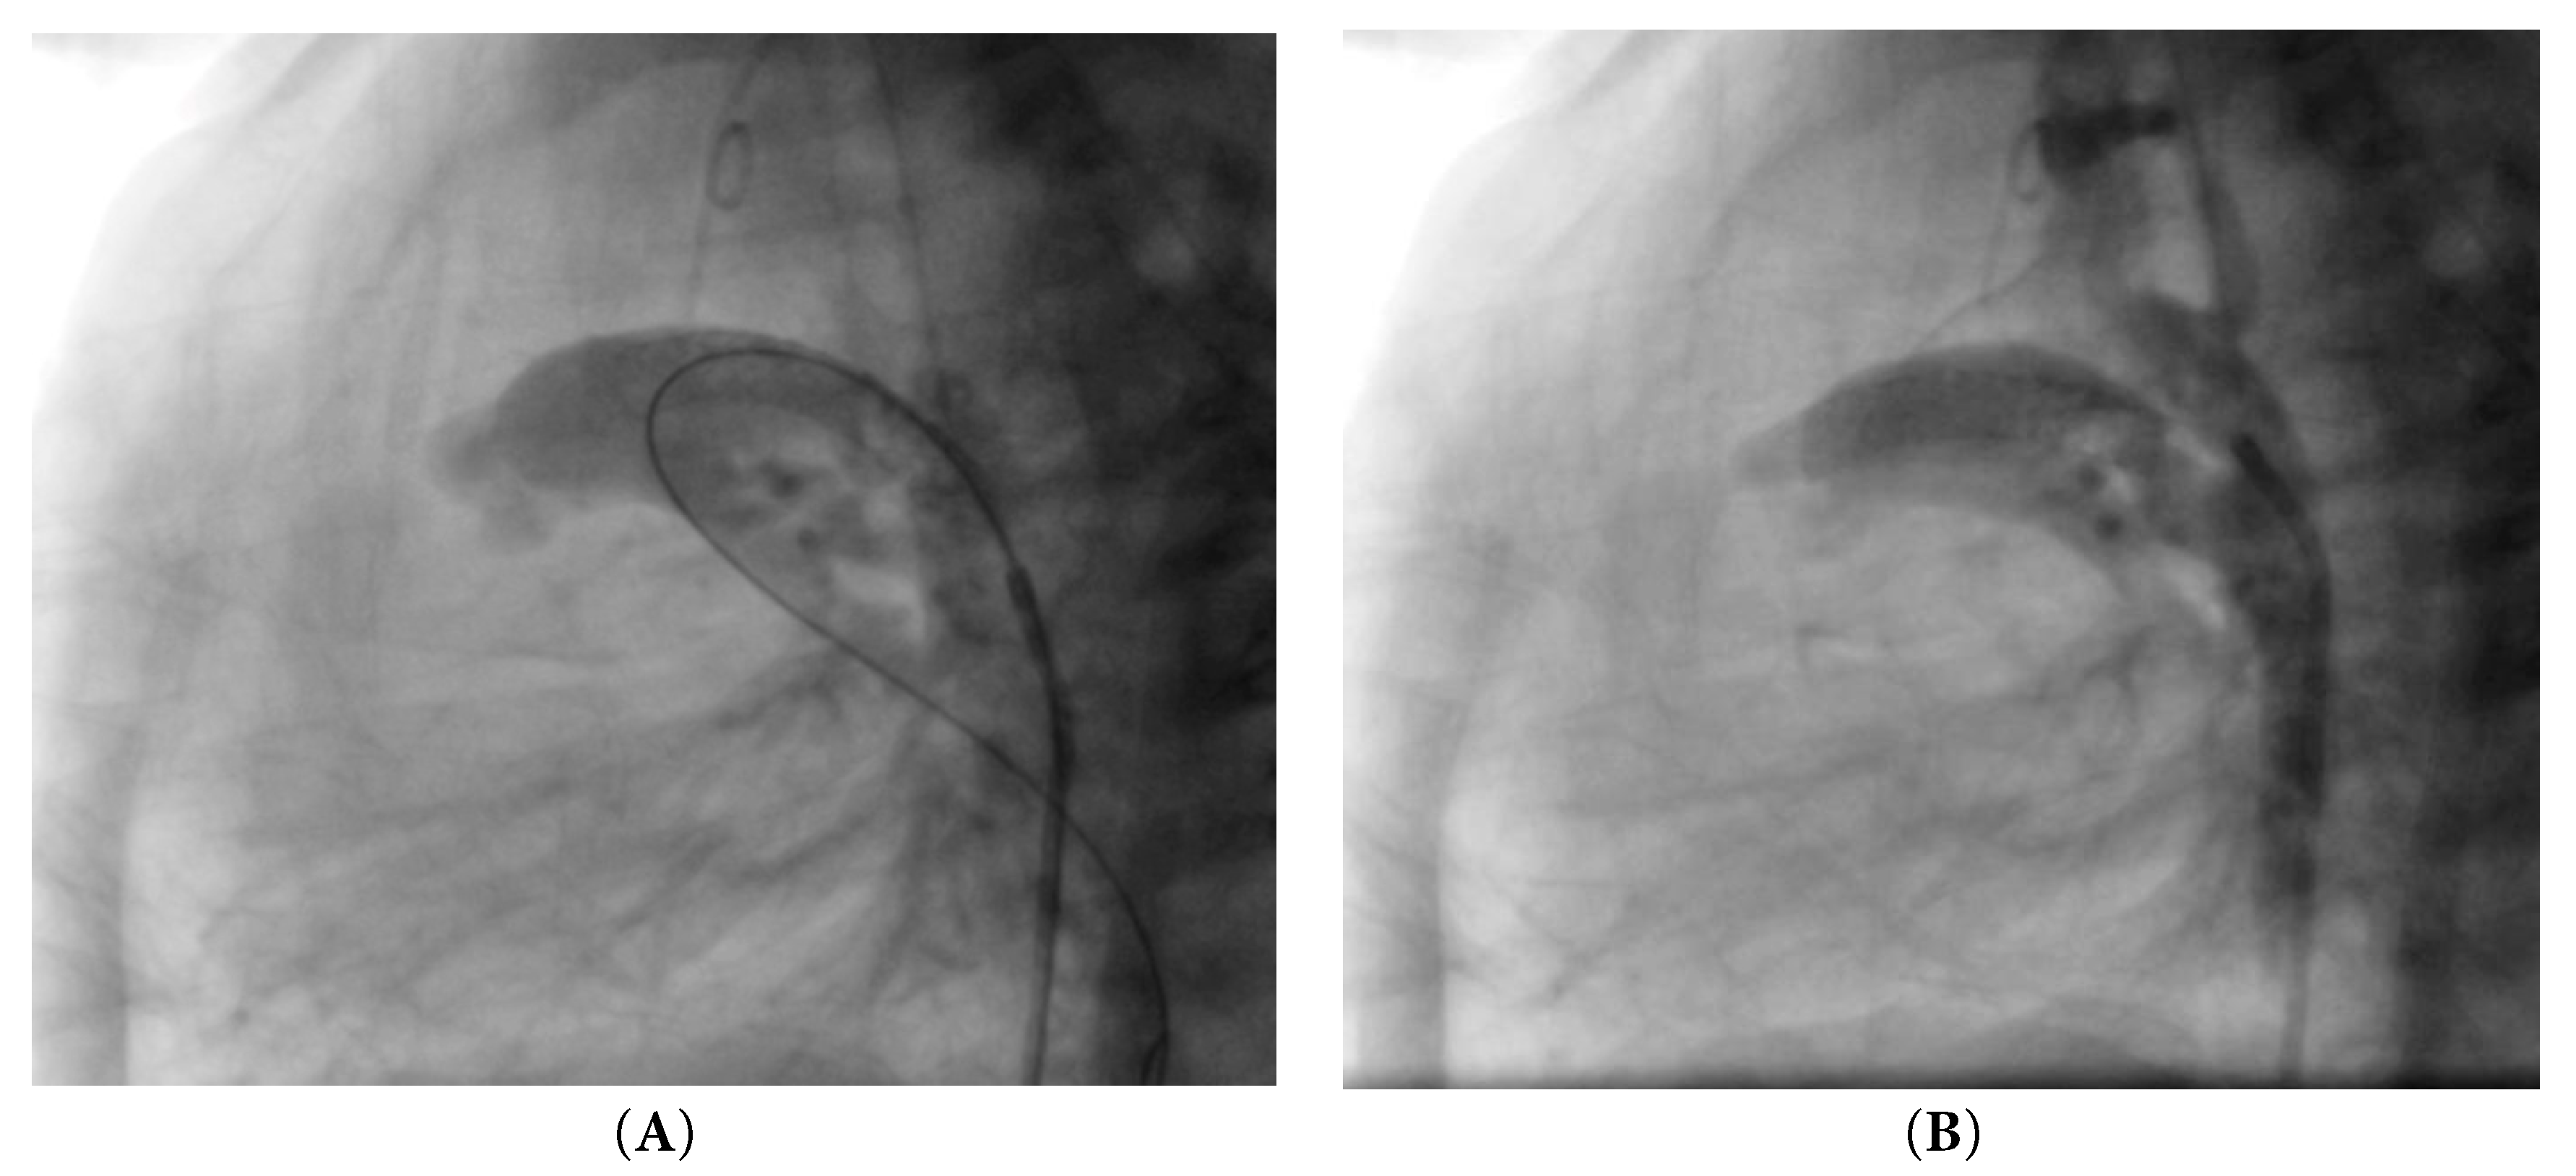

Cardiac catheterization was performed via a retrograde femoral approach using a 4 Fr introducer sheath. Heparin dose of 10 U/kg was infused. The aorta was reached, and the ductus arteriosus was cannulated through the aortic end. A guidewire was advanced into the left pulmonary artery, and the coronary catheter with the mounted stent (Xience SierraTM, Abbott, 23 mm length, 4 mm diameter), was advanced over the wire; the 4 mm diameter was selected based on the patient’s weight at the time of catheterization (2700 g) in accordance with institutional protocol and published recommendations indicating that the duct is stented to 3.5–4 mm in normal term infants weighing 2.5–4 kg [8]. The stent was then deployed with balloon inflation at 12 atmospheres for three seconds. Angiography confirmed stent in position within the ductus arteriosus immediately after implantation, Fig. 1A, and adequate bilateral pulmonary artery flow. Prostaglandin infusion was not resumed after stent implantation, and acetylsalicylic acid (5 mg/kg/day) was started once hemodynamic stability and the absence of bleeding were confirmed.

Figure 1: Angiography. (A) Stent in position immediately after implantation. (B) Stent embolization.

Six hours later, the patient deteriorated, presenting with tachycardia (166 bpm), hypotension (61/29 mmHg), desaturation (67%), along with a respiratory rate of 46 bpm and a temperature of 36.3°C. Arterial blood gas analysis revealed pH 7.34, PCO2 46 mmHg, PaO2 42 mmHg, lactate 5.70 mmol/L, and oxygen saturation 64%. Urgent echocardiography and subsequent angiography showed complete embolization of the stent into the main pulmonary artery, Fig. 1B, resulting in cessation of ductal flow. Given the patient’s profound instability, characterized by severe desaturation and bradycardia following stent embolization into the main pulmonary artery, immediate surgical intervention was prioritized. The critical condition did not allow for an attempt at a second stent, and the patient was therefore taken urgently to the operating room.